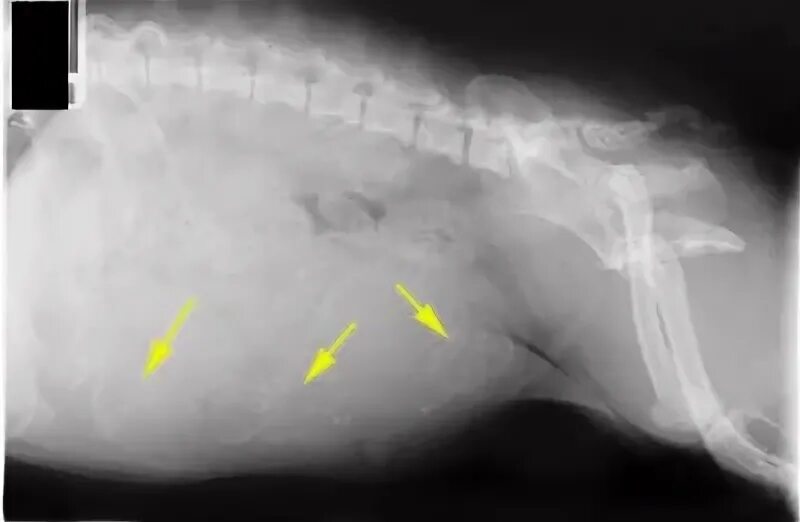

Петля после вязки